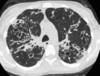

8

Q

Patrón de consolidación alveolar

A

Aumento de la atenuación pulmonar

How well did you know this?